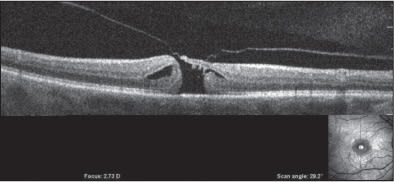

• Case Report: SC is a 62-year-old white woman with the chief complaint of distortions and vision loss in the right eye of three months' duration. Visual acuity was 20/200. Combined OCT/SLO demonstrated anomalous PVD with persistent adhesion of the posterior vitreous cortex to the fovea and underlying macular hole and cysts (Figure 3). She underwent injection in the office and two days later described the sudden onset of a “kaleidoscope effect.” One week after injection the distortions were much reduced and vision improved. Visual acuity was 20/40. Combined OCT/SLO demonstrated complete PVD with closure of the macular hole and no evidence of cysts (Figure 4). The elevation of the fovea, which is sometimes seen following surgical closure of macular holes, persisted for 15 months before resolving spontaneously (Figure 5).

Figure 3. Anomalous PVD with macular hole. CombinedOCT/ SLO imaging demonstrates anomalous PVD with persistent vitreo-foveal adhesion inducing a full-thickness macular hole and adjacent cystoid spaces.